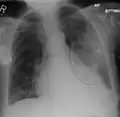

Normal AP CXR

Normal lateral CXR -

Right lower lobe pneumonia as seen on a lateral CXR